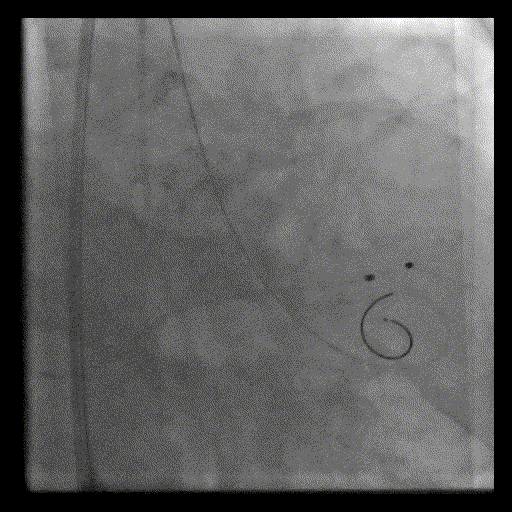

完全释放并撤回输送系统

最终造影

微量瓣周漏

植入后造影微量反流,超声提示瓣膜工作良好,最大跨瓣流速1.7m/s,平均跨瓣压差几乎为0,造影检查主入路,血管未见损伤,手术顺利结束。